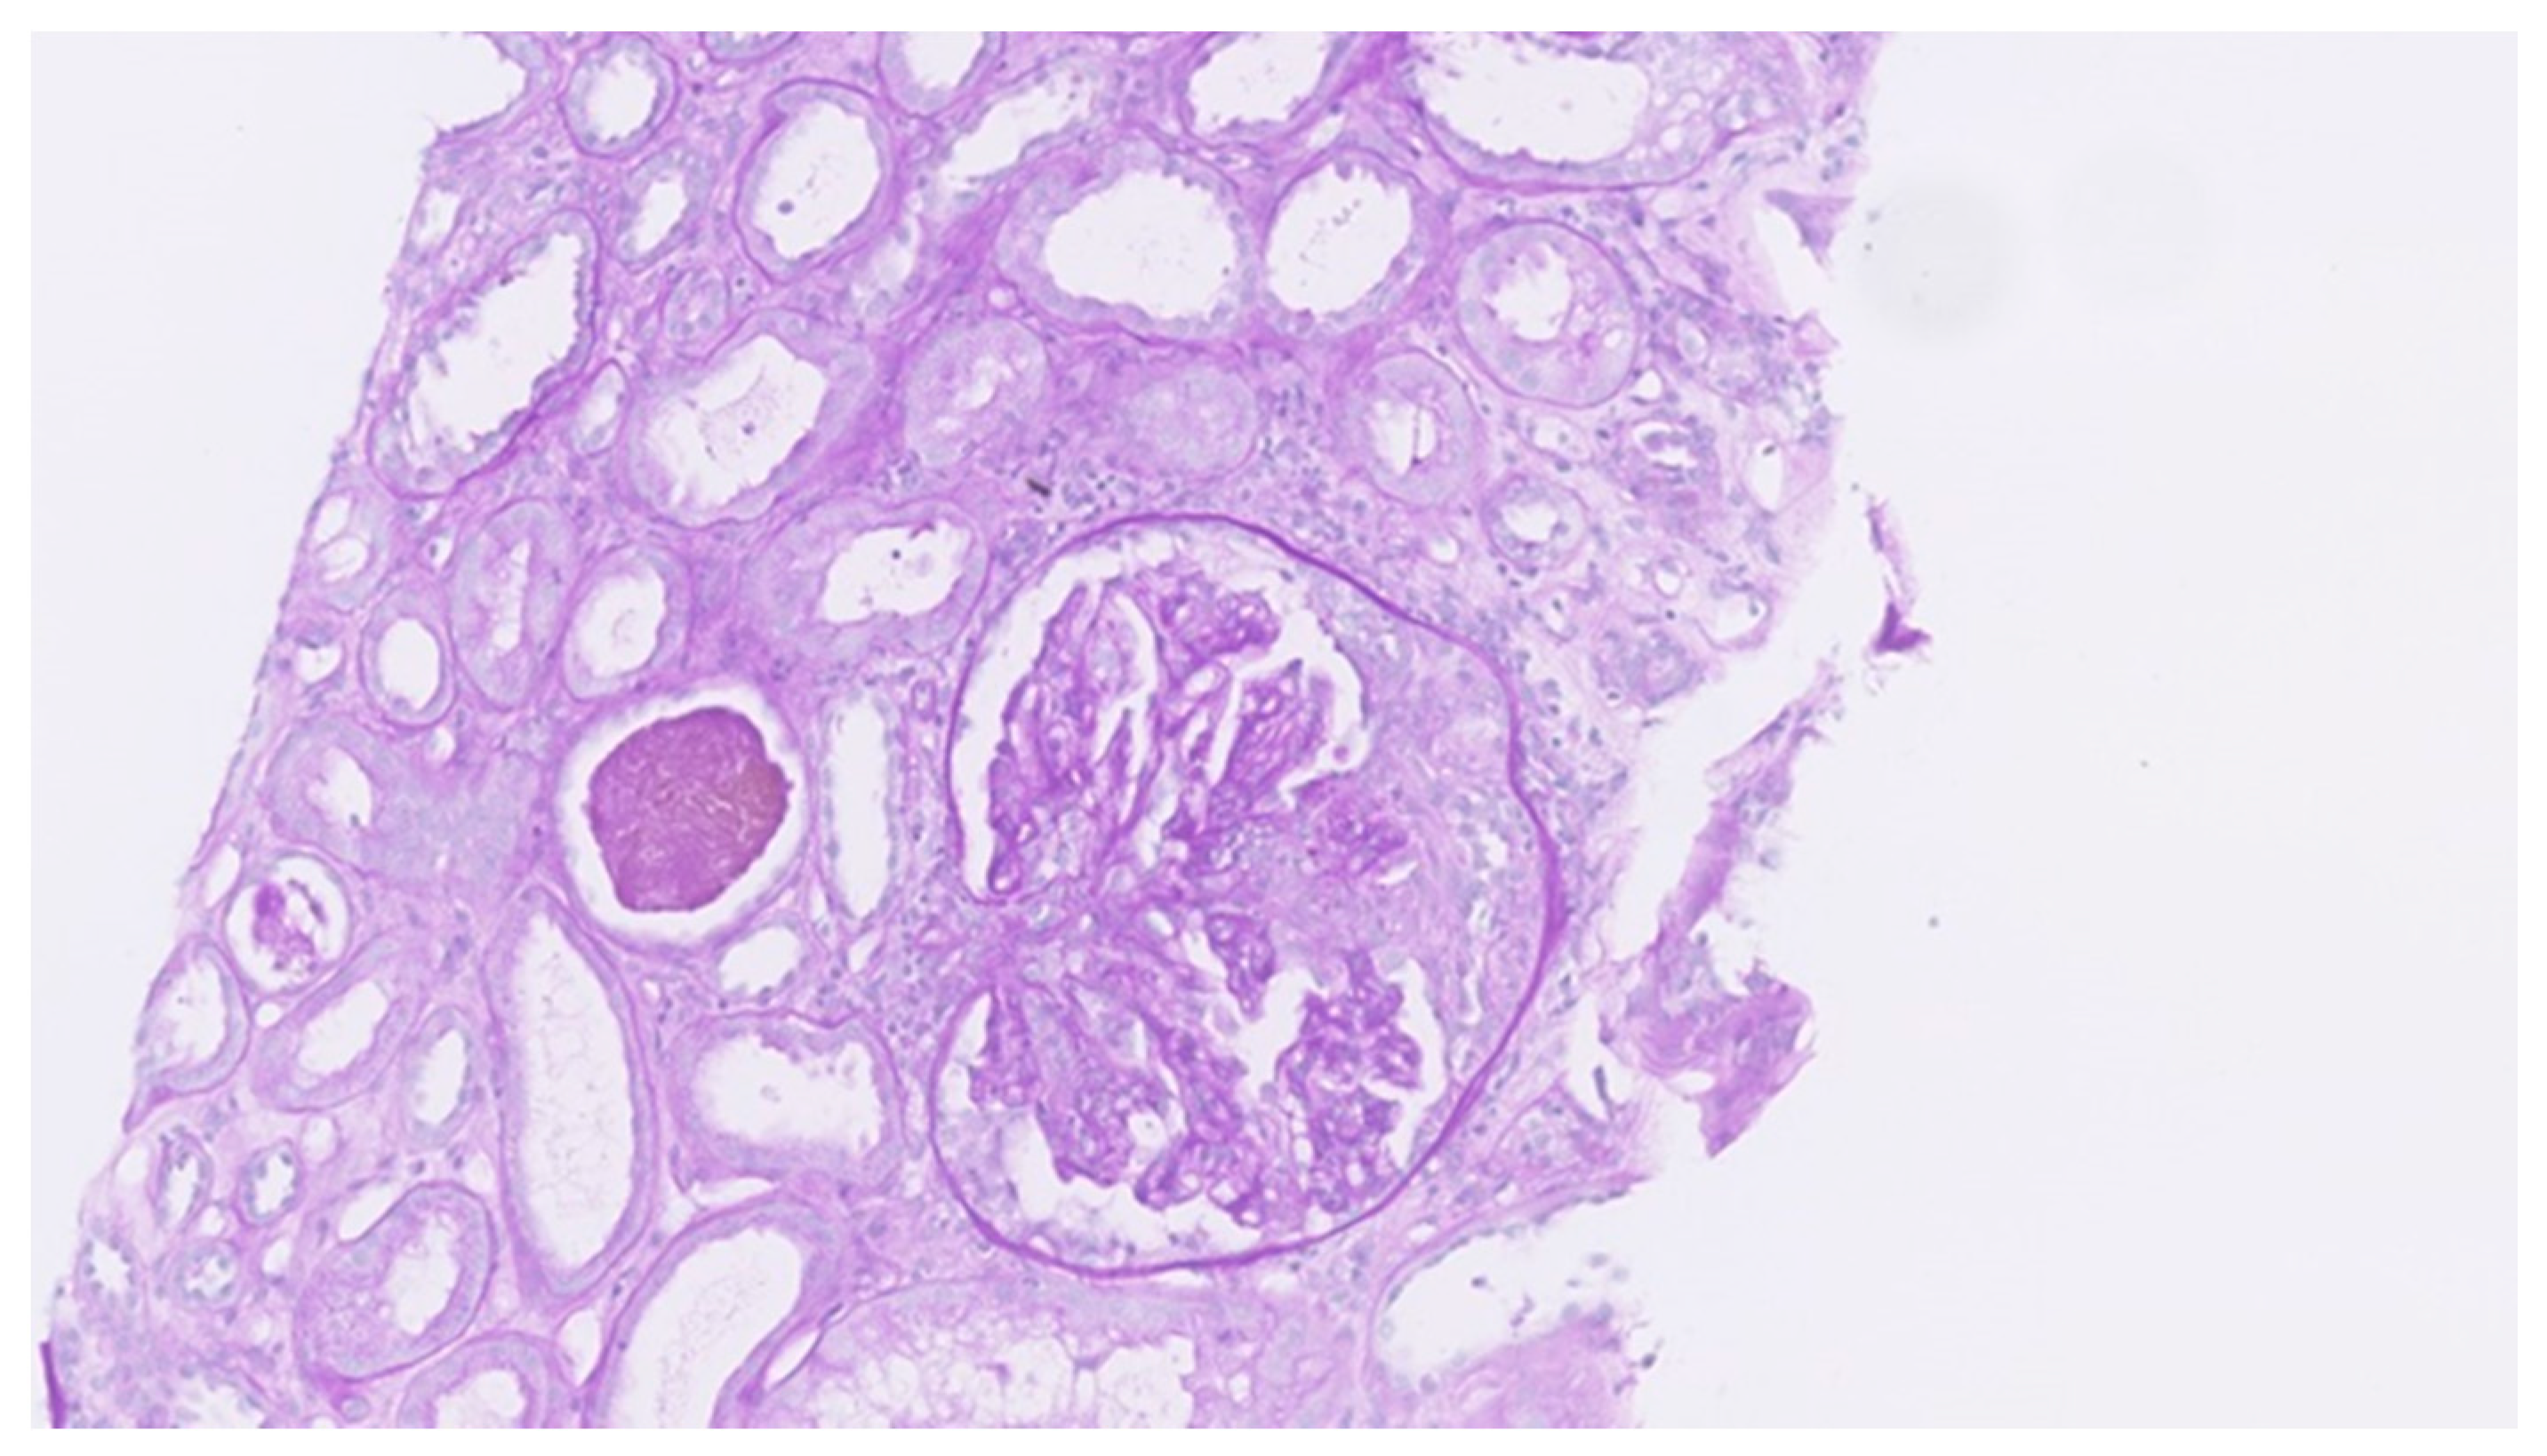

Uncommon Presentation of Granulomatosis with Polyangiitis Mimicking Metastatic Lung Cancer

3. Results